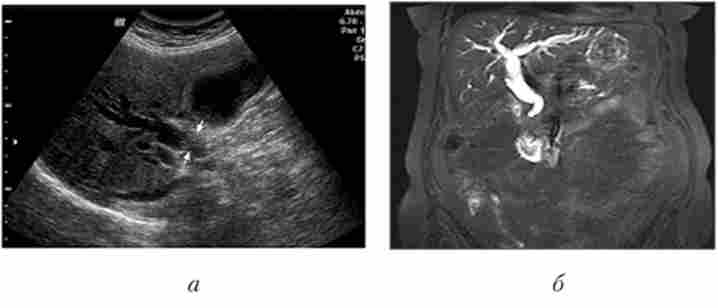

Мал. 5.1.Пухлина загальної жовчної протоки:

а - в ультразвуковому зображенні видно «обрив» жовчної протоки в області його звуження гіперехогенной пухлиною; б - МРТ, тривимірне зображення: кукса конично звуженого пухлиною протоки, проксимальні відділи гепатікохоледоха і печінкові протоки розширені внаслідок біліарної гіпертензії